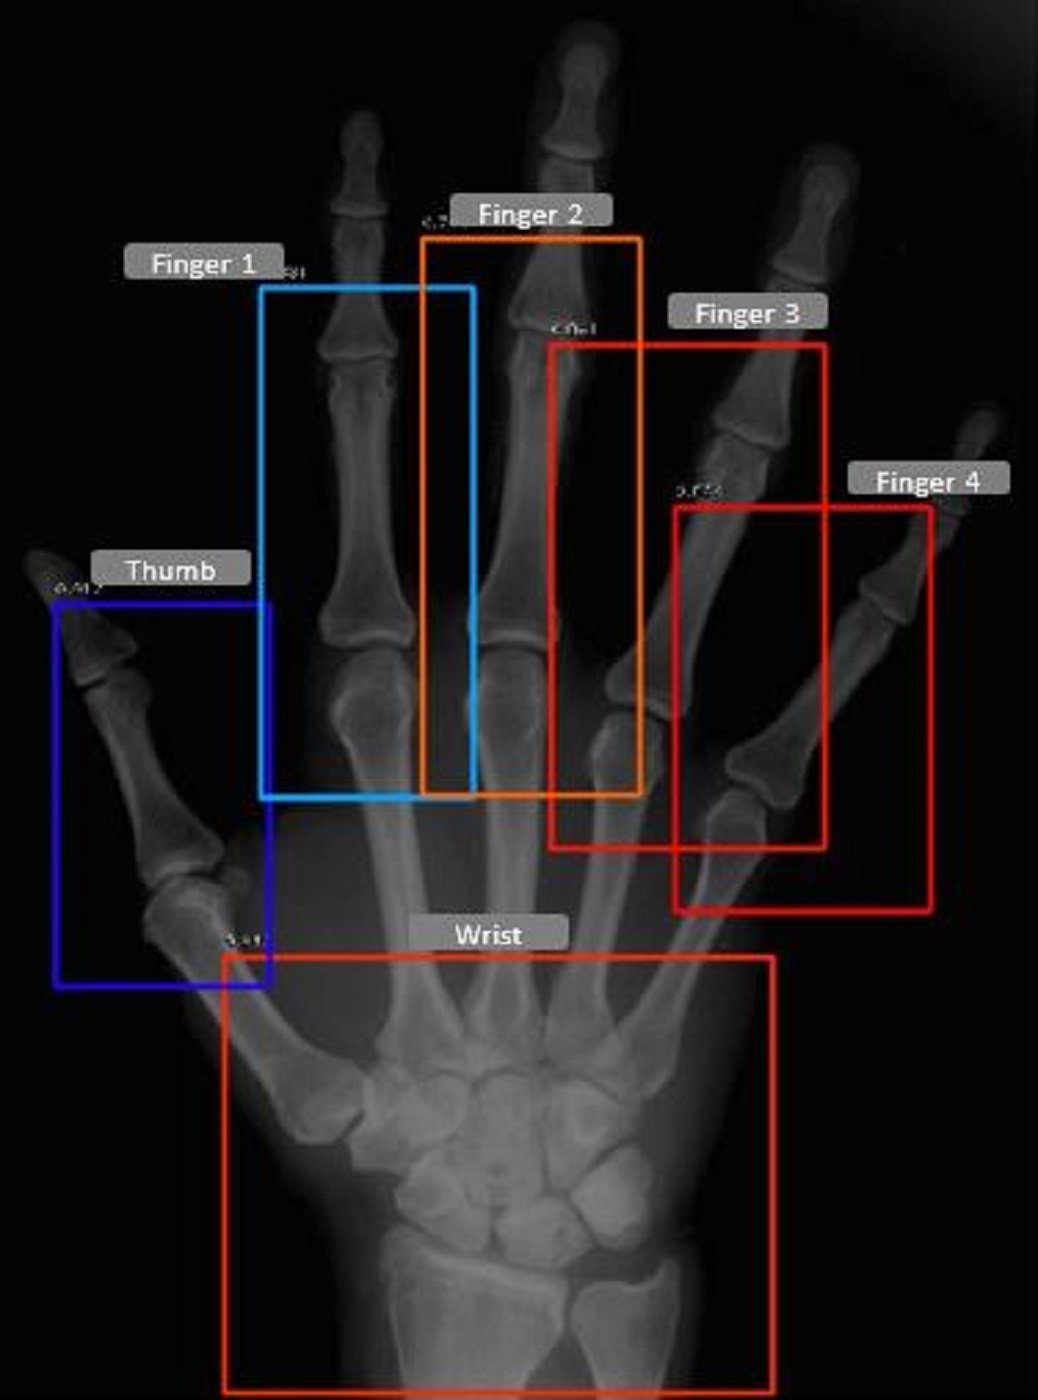

Refer to caption

(a) Hand Fingers/Wrist detected by the model

Figure 3: Fingers, wrists and thumb/toe identified by the detection models for a patient

We evaluate the detector models on the test dataset which comprised of 50 Hands/Feet radiographs respectively, these radiographs were not used during the training and validation. The detector model, for the feet was able to achieve a mAP of 0.965, whereas the hand model achieved a mAP of 0.981 at an intersection over union threshold (IOU) of 0.6. In Table 1, we report the joint wise average precision (AP), we observe that the wrist joint being the easiest to detect, achieves the highest AP, whereas all other joints have a relatively similar AP in the case of both detector models. Fig. 4 represents the joints detected for a patient in the test set.

Thumb/Toe 0.986 0.983

Finger 1 0.979 0.973

Finger 2 0.983 0.955

Finger 3 0.971 0.947

Finger 4 0.977 0.965

Wrist 0.993 -

Overall mAP 0.981 0.965